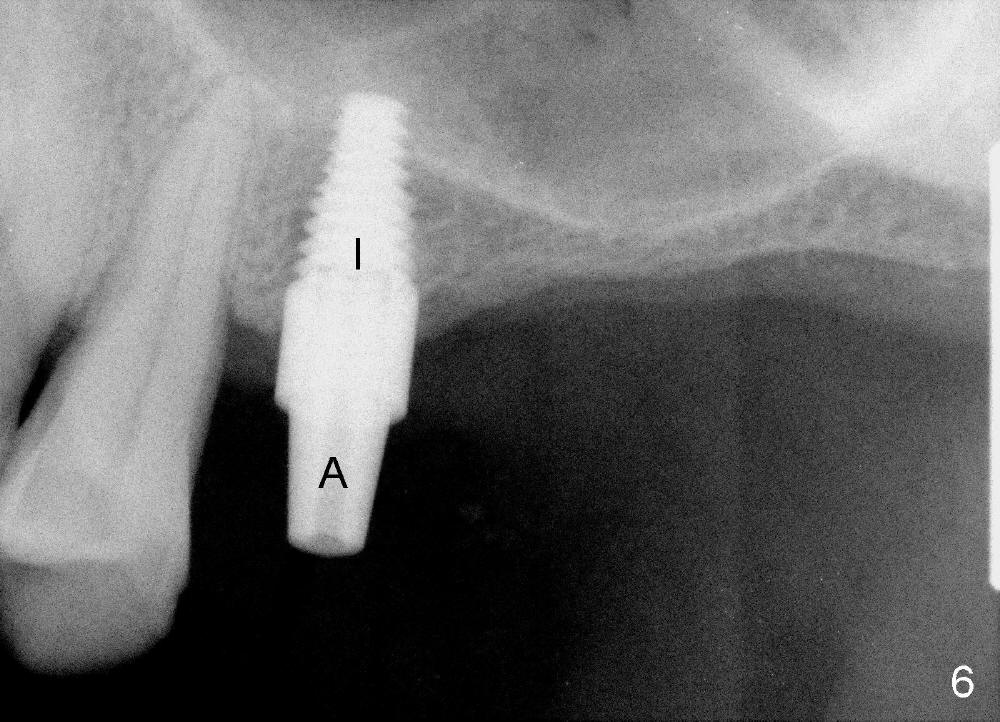

placed relatively ideally (Fig.6 I with insertion torque 60 Ncm). A

restorative abutment (A) is placed immediately for a provisional (immediate

loading). There is no nasal hemorrhage intra- or post-op.